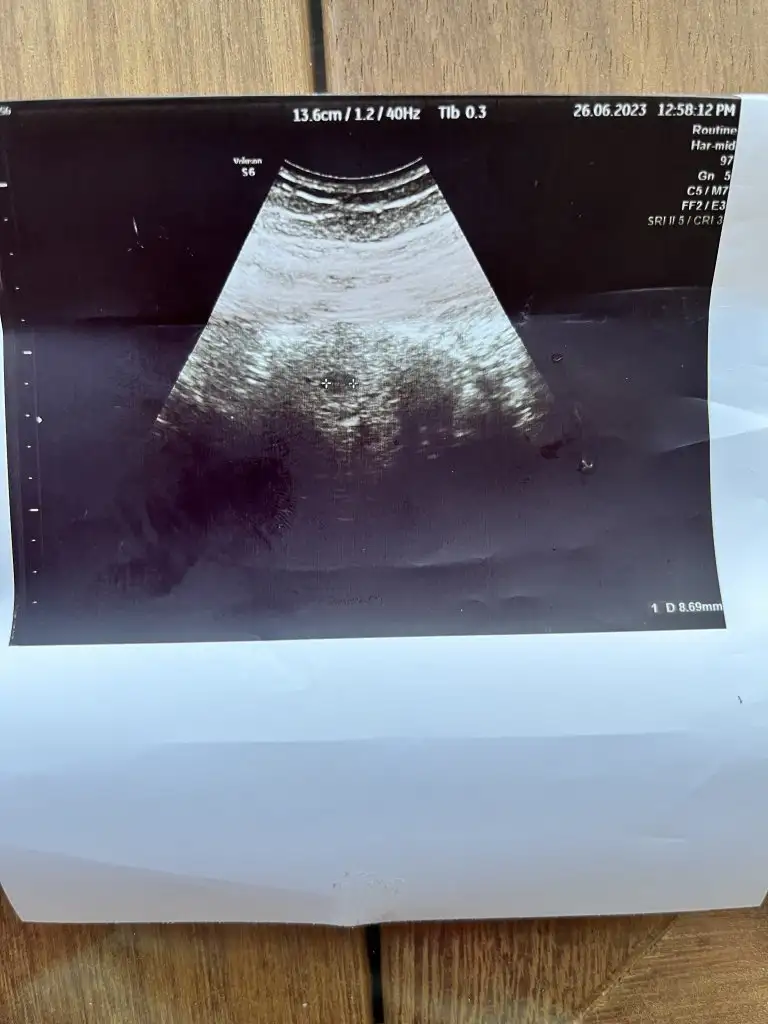

Beta artısı kese oluşana kadar önemli diye duymuştum kese görüldüyse tamamdır beta önemli değilBende bugün doktora gittim, bayram sonrasına gidecektim ama git gel 12 saat yolculuk yaptığım için merak ettim gittim.sat a göre 6+1 im bugün. Doktor karından keseye baktı gördük 8.6mm. İçinde bebeği göremedik henüz haftaya gel dedi görürüz dedi ama içim içimi yiyor keşke görebilseydik diye. Sonra betana bakalım yüksekmiş mi dedi. Kanı verdik çıktık hastaneden. Geçen pazartesi beta 1300 çıkmıştı yine bugün pazartesi 8900 çıkmış aradı doktor güzel değerin yükselmiş dedi. Artış sanki az geldi bana kızlar ne bileyim 2 günde bir iki katı artarsa 15000 falan hesaplamıştım kafamda. Normal mi sizce başına böyle bişey gelen oldu mu. 6+1 kese 8.6 mm karından baktı o yüzden mi bebek görünmedi henüz çok yeni gebelik dedi kötü düşünmek istemiyorum ama haftaya kadar içim içimi yiyecek

Kese görüldükten sonra betanın önemi kalmıyor pekBende bugün doktora gittim, bayram sonrasına gidecektim ama git gel 12 saat yolculuk yaptığım için merak ettim gittim.sat a göre 6+1 im bugün. Doktor karından keseye baktı gördük 8.6mm. İçinde bebeği göremedik henüz haftaya gel dedi görürüz dedi ama içim içimi yiyor keşke görebilseydik diye. Sonra betana bakalım yüksekmiş mi dedi. Kanı verdik çıktık hastaneden. Geçen pazartesi beta 1300 çıkmıştı yine bugün pazartesi 8900 çıkmış aradı doktor güzel değerin yükselmiş dedi. Artış sanki az geldi bana kızlar ne bileyim 2 günde bir iki katı artarsa 15000 falan hesaplamıştım kafamda. Normal mi sizce başına böyle bişey gelen oldu mu. 6+1 kese 8.6 mm karından baktı o yüzden mi bebek görünmedi henüz çok yeni gebelik dedi kötü düşünmek istemiyorum ama haftaya kadar içim içimi yiyecek

Canım kese göründü ise betayi boşver,Bende bugün doktora gittim, bayram sonrasına gidecektim ama git gel 12 saat yolculuk yaptığım için merak ettim gittim.sat a göre 6+1 im bugün. Doktor karından keseye baktı gördük 8.6mm. İçinde bebeği göremedik henüz haftaya gel dedi görürüz dedi ama içim içimi yiyor keşke görebilseydik diye. Sonra betana bakalım yüksekmiş mi dedi. Kanı verdik çıktık hastaneden. Geçen pazartesi beta 1300 çıkmıştı yine bugün pazartesi 8900 çıkmış aradı doktor güzel değerin yükselmiş dedi. Artış sanki az geldi bana kızlar ne bileyim 2 günde bir iki katı artarsa 15000 falan hesaplamıştım kafamda. Normal mi sizce başına böyle bişey gelen oldu mu. 6+1 kese 8.6 mm karından baktı o yüzden mi bebek görünmedi henüz çok yeni gebelik dedi kötü düşünmek istemiyorum ama haftaya kadar içim içimi yiyecek